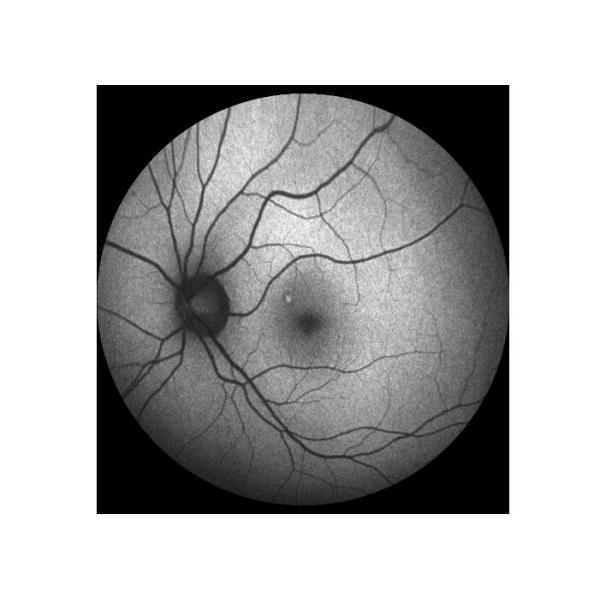

Angiografía del verde de Indocyanine (ICGA) Buques coroides y lesiones de RPE |

1) Estándar de oro para la diagnosis del PVC 2) Para revelar los detalles del ciclo coroides 3) Suplemento a FFA, encontrar CNV latente desapercibido en FFA 4) Para reflejar principalmente los vasos sanguíneos condicionan en etapa temprana y media, en última etapa para reflejar la forma y la función de las células de RPE |